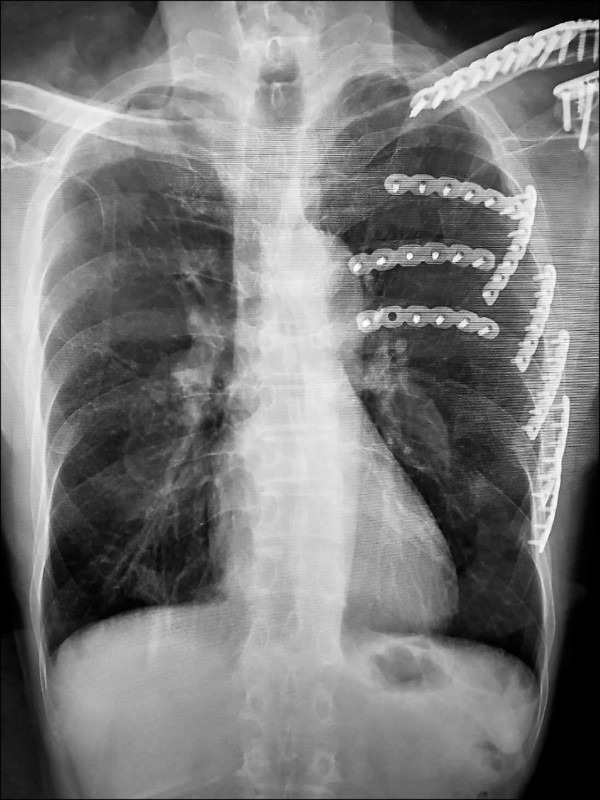

台中一名70歲陳姓老翁日前遭遇嚴重車禍,左側第3到第7根肋骨全數斷裂,還出現胸壁挫傷跟血胸狀況,幾乎無法正常呼吸。他被緊急送往國軍台中總醫院急救,醫療團隊準備為他進行「胸腔鏡輔助肋骨骨折復位矯正鋼板內固定手術」,沒想到術前檢查電腦斷層時,胸腔外科主任謝志明竟在影像中發現更可怕的東西。

根據《TVBS新聞網》、《自由時報》報導,謝志明主任仔細分析陳先生的斷層掃描影像,赫然發現他的右下肺葉出現疑似癌症的病灶。當時陳先生的車禍傷勢在住院治療2週後就順利出院,但那塊毛玻璃樣的肺部陰影卻讓醫師相當擔憂。由於肺腺癌被稱作「隱形殺手」,早期幾乎沒有任何症狀,許多患者發現時往往已經來不及了。

圖片來源:國軍台中總醫院

3個月後陳先生回診追蹤肋骨復原狀況,謝醫師發現那處病灶依舊存在,立刻安排他接受第2次「胸腔鏡微創手術」將病灶切除。病理化驗結果證實醫師的判斷沒錯,陳先生確實罹患肺腺癌第1期。謝醫師解釋,一般胸部X光很難偵測到1公分以下的微小病變,許多肺癌病患確診時病情已經相當嚴重。